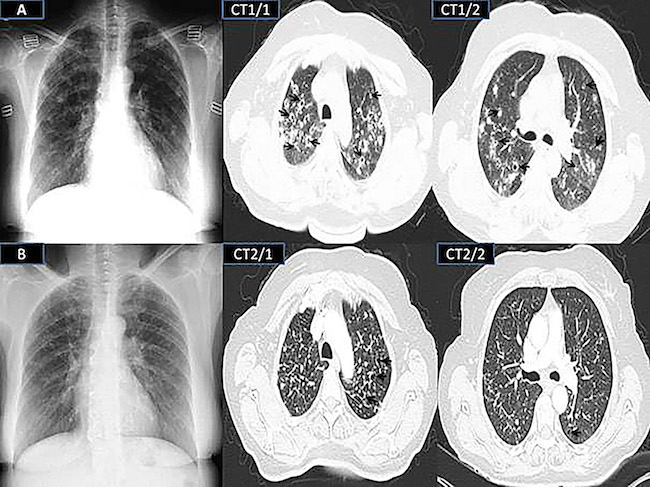

A 52-year-old female patient was admitted to our outpatient clinic with complaints of chest pain, cough, sputum dyspnea, and weight loss, which was started three weeks ago. The patient with diabetes mellitus was under immunosuppressive therapy for five years due to drug-resistant ITP. Our patient also had a history of splenectomy due to refractory thrombocytopenia. In the last year, the patient's treatment was daily 50 mg azathioprine and 4 mg methylprednisolone. On examination, the patient's temperature was 38° C. The respiratory rate was 25 min and the pulse rate was 95 beats/min. In auscultation, the inspiratory crackles were heard on both hemithorax. WBC counts were 17,600 mm3 and platelet counts were 29,000 mm3. Oxygen saturation measured by the pulse oximeter was 97%. Chest X-ray showed diffuse reticular opacities that were more prominent in the upper zones of both lungs (Fig. 1).

The patient was hospitalized with suspicions of opportunistic pulmonary infection and cavitary lung disease. Empirically, intravenous piperacillin-tazobactam (3x4.5 g/day) and oral clarithromycin (2x500 mg/day) were started. Thorax CT revealed many thin-walled cavities and millimetric nodules accompanied by ground-glass infiltrates in the upper and middle lobes of both lungs (Fig. 1). Most of the nodules, which one of the largest has 17x12 mm in diameter, predominantly were located in the peripheral areas (Fig. 1). The disease which could develop cavities in the lung, such as tuberculosis, rheumatic lung diseases, vasculitis syndromes, and fungal infections were excluded by using acid-fast bacilli staining and Gram staining, serum and blood galactomannan levels, and vasculitis markers.

Empirical treatment was continued for 21 days because the sensitivity was detected. After the treatment, the patient's clinical and radiological findings regressed significantly, and he was discharged with outpatient follow-up. At the 12th months of follow-up, thoracic CT taken for transient dyspnea revealed that pulmonary infiltrates were significantly reduced and only sequelae cavitary lesions could be observed (Fig. 1).